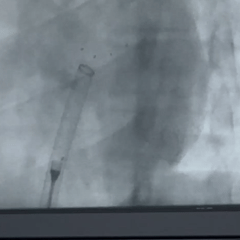

前抵鞘管,逆时针旋拧钢缆,封堵器释放,DSA下,5个mark点相对位置不变

释放后观察

封堵器位置正确、夹持稳定、形态良好、无残余分流,封堵手术成功